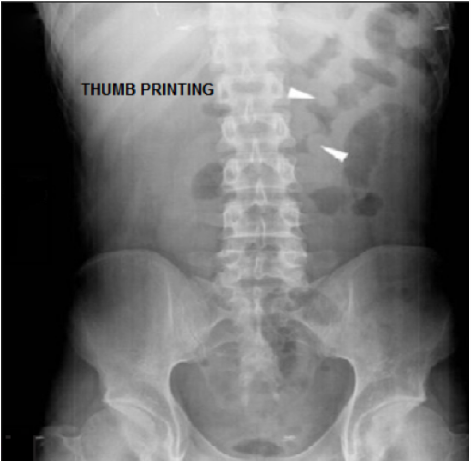

Thumbprinting sign is suggestive of _____

The thumbprinting sign is seen in both _____ colitis and _____ colitis.